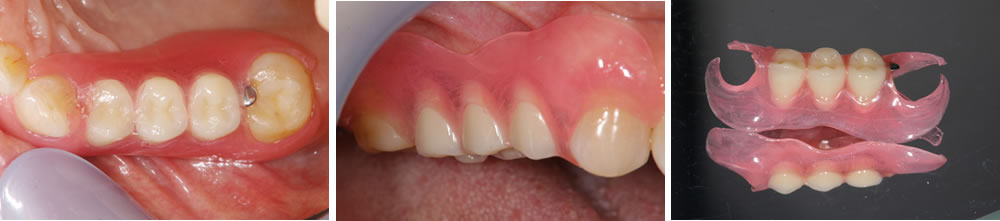

金属に嫌悪感がある患者に対して欠損部をノンクラスプデンチャーで改善した症例

こちらは右上の歯茎が痛いという主訴で来院された患者さまです。

10年以上前に金属が嫌で右上の金属の被せ物を除去してもらって、そのままになっているとのことでした。しっかり噛めるようにしたいが金属には抵抗があるので金属は入れたくないとの要望がありました。

こちら患者さまは、金属が口腔内に入ったままの状態が嫌で、被せ物を外した状態で放置していた歯が多数あり、奥歯に保存不可能な歯が残っているという状態でした。しっかり噛めるようにしたいという要望があり、インプラント治療を提案しましたが、金属に対して抵抗感が強かったため、インプラント治療は行いたくないとの事でした。

保存不可能な歯は抜歯し、欠損部に関しては自費で作成する金具を用いない入れ歯(ノンクラスプデンチャー)で治療し、保存可能な歯はセラミックで治療するという計画としました。

ノンクラスプデンチャーの装着・治療完了

インプラント治療ではなく、右上欠損部をノンクラスプデンチャーで治療しましたが、右上7番を保存することができた事によって、ノンクラスプデンチャーが前後の歯でしっかりと安定した状態を作る事ができました。それによって、患者さんのしっかり噛みたいという要望にも応える事ができ、非常に満足されていました。

入れ歯の沈み込み防止のために、最後方の歯には強度のあるメタルレストを使用させて頂きましたが、取り外しのできるものでこれぐらいなら気にならないとの事でご了承頂きました。歯に引っかける部分に金属を使用していないので、装着時も目立たずに見た目も気にならないので嬉しいとおっしゃっていました。